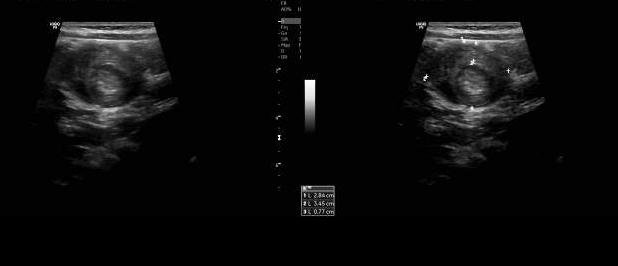

Solicita-se instilação de 2 tubos de Minilax com avaliação da evacuação insatisfatoria. Vinte minutos depois a criança começa com uma nova série de colicas, doloridas, é alojada na sala de tratamentos e infundem-se 0,4 ml Buscopan em bolus e. v. com resposta positiva imediata, solicitando-se uma hemograma e uma coleta urinaria por sonda. Mantida na sala de observação. Resultados: hemograma absolutamente normal, urina negativa para ITU. No entanto, as colicas voltam, e como já tinham passado 2 horas da ultima administração, repita-se a dose de buscopan e. v.. Depois de passar o ultimo episodio álgico, solicita-se uma nova lavagem intestinal, desta vez com Fleet Enema. Com essa segunda lavagem a criança evacua uma amostra de fezes pastosas, com muito muco e de cor discretamente avermelhada, que parece 'geleia de morango'. Passado um intervalo de tempo depois da segunda lavagem, as dores voltam, criança recebe a terceira dose de buscopan e é solicitado US de abdomen. Laudo: ' - Ausência de liquido livre na cavidade abdominal. Bexiga com capacidade normal, paredes finas e regulares e conteúdo homogêneo. Estudo ultrassonográfico dirigido para região abdominal, evidencia-se no presente momento formação em aspecto de 'lesão em alvo', na topografia do hipogástrio, medindo 2,5 x 3.5 cm, com camada externa de 0,8 cm de espessura, sem caracterização de causa secundária pelo método ecográfico.'

Intussucepção intestinal. (0,05 pontos)

DISCUSSÃO: A intussuscepção é a causa mais frequente de obstrução intestinal em lactentes e préescolares. É uma emergência, ocorre com maior freqüência em crianças com idade abaixo dos dois anos. Depois da apendicite, é a segunda mais comum emergência abdominal na criança. A dor abdominal é súbita e cessa de modo tão repentino quanto seu início. A criança pode parecer confortável, mas eventualmente pode ser tornar letárgica. A dor abdominal é caracterizada pelo choro da criança e pela flexão das pernas em direção ao abdome. Os paroxismos de dor costumam acompanhar-se de esforços para defecar e as fezes em 'geléia-de-framboesa', de modo geral, aparecem nas primeiras 24 horas, mas em raras ocasiões surgem até dois dias após o início do quadro. Ao exame físico, o sinal mais consistente é a presença de massa palpável, de aspecto tubular, no quadrante superior direito do abdome, podendo ser subcostal. Esta pode ser mal definida e de consistência amolecida.

DISCUSSÃO: Esclarecemos desde o início que as radiografias têm valor limitado, como ferramenta de triagem, quando achados sugestivos são encontrados. NÃO utilizar na CONFIRMAÇÃO do diagnóstico e NÃO utilizar como um ÚNICO TESTE para o diagnóstico. A ULTRASSONOGRAFIA é a ferramenta de triagem para a grande maioria das instituições.